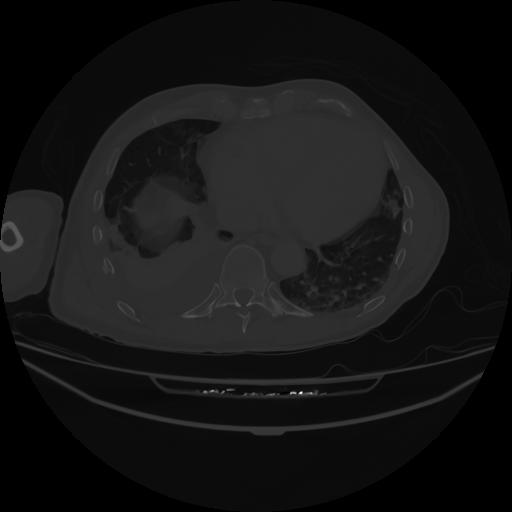

5 CUERPO,CE,Vol,1.0,CUERPO,,